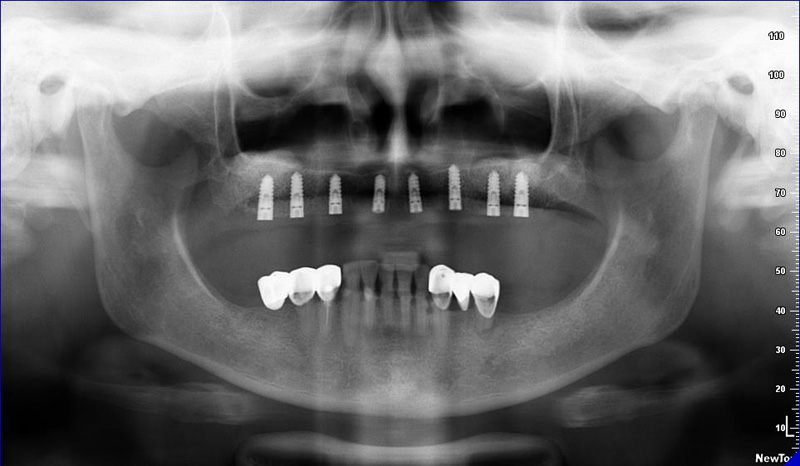

Zásadním faktorem pro úspěšné ošetření je přesná a detailní diagnostika a dokonalé naplánování celého ošetření. K tomu vždy využíváme kombinaci zjištění z klinických vyšetření a rentgenologických dat, které následně zpracováváme v plánovacím softwaru.

Jak pro ošetření stomatochirurgická tak implantologická spolu různými dostavbami kosti je vždy nutné předem znát umístění důležitých anatomických struktur (cévy, nervy, čelistní dutiny). Naše pracoviště jako první v České republice začalo

od roku 2004 používat speciální digitální zubní tomograf 3D DVT NewTom a dále také využíváme nejnovější hybridní CBCT (3D) + 2D přístroj NewTom GiANO, které umožňují 100% diagnostiku množství a kvality kosti a veškerých důležitých anatomických struktur.

Pro následné plánování využíváme počítačové programy NewTom Implant Planning a coDiagnostiX, které slouží na plánování vhodných pozic pro zavedení implantátů, operačních šablon, kostních bloků, pozdějších protetických náhrad, ...

Pomocí tohoto přístroje je možné zjisti skutečnou situaci v čelistních kostech pacienta tedy množství kosti - můžeme změřit skutečnou šířku i výšku kosti, i kvalitu kosti (hustotu) v místě uvažované implantace. 3D (tříprostorové) zobrazení umožňuje

zvýšit prostorovou představu operatéra ještě před vlastní operací a zároveň pacientovi lépe objasnit a ukázat oblast plánovaného zavedení implantátu.

Pacient „neumí číst“ RTG snímky, ale díky 3D zobrazení vidí „svoji skutečnou čelist“ – např. jak je nízká či úzká, vidí průběh nervu nebo velikost čelistní dutiny, což mu umožní i pochopení nutnosti v některých případech provést pomocné zákroky

ještě před vlastním zavedením implantátu (více - Augmentace - kostní štěp, sinus lift, kostní granulát...).